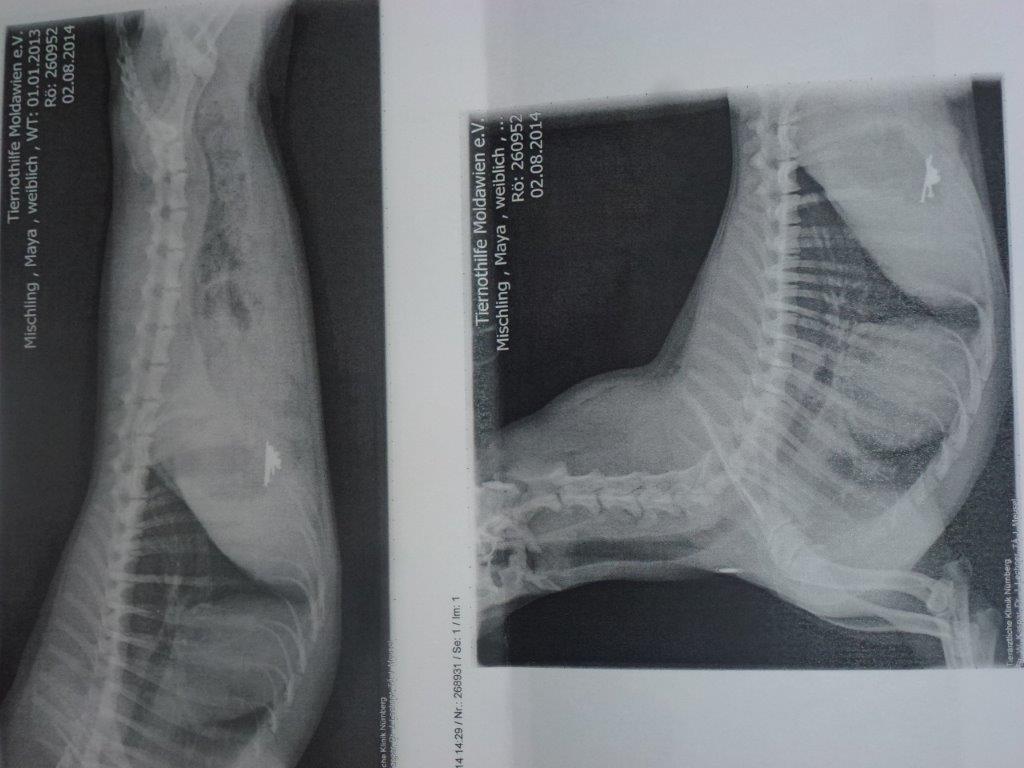

Am 02.08. haben wir wieder einmal gemerkt, dass es auch in Deutschland die absoluten Hundehasser gibt. Wir sind wütend , traurig und sehr geschockt. Unsere süße Maya hat heute einen Giftköder erwischt, der bei meinen Eltern im eigenen Garten in Lauf ausgelegt war.Frischwurstaufschnitt, gefüllt mit Rattengift und Schneckenkorn und weil das nicht reicht, gleich noch ein paar Nägel obendrauf. Die kleine Maus liegt jetzt in der Tierklinik und kämpft um ihr Leben. Ich wünsche demjenigen alles Schlechte dieser Welt, denn dieser arme Hund hat niemandem etwas getan.

Zum Glück ist die süße Maus eine Kämpferin und hat nach einer Endoskopie, mehreren Magenspülungen und verschiedensten Medikamenten nach 24 Stunden die Klinik wieder verlassen können. Jetzt werden wir diesen Hundehasser anzeigen und ihm die Polizei auf den Hals hetzen, denn das hätte alles ganz anders enden können.